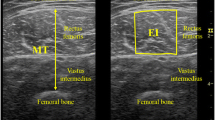

EI

Transversal ultrasonic images were acquired from the rectus femoris (RF) and vastus lateralis (VL) three times using an ultrasonic apparatus (ACUSON S3000; Siemens Medical Solutions, USA) coupled with a linear transducer array (9 L4 Transducer, 4–9 MHz, 4 cm footprint, Siemens Medical Solutions). The participants sat on the dynamometer seat with hip flexed at 80° and knee flexed at 90°, and they were asked to relax completely. The measurement sites of EIRF and EIVL were at 50% of thigh length from the greater trochanter to the articular cleft between the lateral femoral condyle and lateral tibial condyle in the longitudinal direction, and at the center of each muscle width in the transverse direction. The ultrasonography settings remained constant for all participants; specifically, depth, focus, and gain of the ultrasonic image were 6 cm, at top of the image, and 90 dB, respectively. The depth of 6 cm was selected because we expected any muscle thickness of the participants did not exceed 6 cm. Prior to the EI measurement, the participants were resting in the seated position for 10 min to eliminate potential effects of fluid shift. For each ultrasonic image, EI was computed as the mean value of gray scale expressed in arbitrary units as a value between 0 (black) and 255 (white) within a region of interest (ROI) using image processing software (ImageJ; National Institutes of Health, Bethesda, MD). The ROI covered as much muscle as possible without aponeuroses, fascia, or nontarget muscles. The EI values measured in each of the three separate images collected, were averaged for each muscle (RF and VL), and the mean EI values were used as representative values for further analyses. The analysis of EI was conducted by the same investigator (RA).

In the present study, specific muscle strength was defined as the MVIC torque per muscle volume. MVIC torque measurement was described earlier. Muscle volume was estimated from the anterior thigh thickness and thigh length using an equation provided by a previous study (Nakatani et al. 2016). For muscle thickness measurement, transversal ultrasonic images were obtained at 50% of thigh length in longitudinal direction, and forefront of the thigh in transverse direction using the ultrasonic apparatus. The participants were asked to stand upright with their feet shoulder-width apart. Muscle thickness was evaluated as a distance between upper surface of RF and that of the femur.